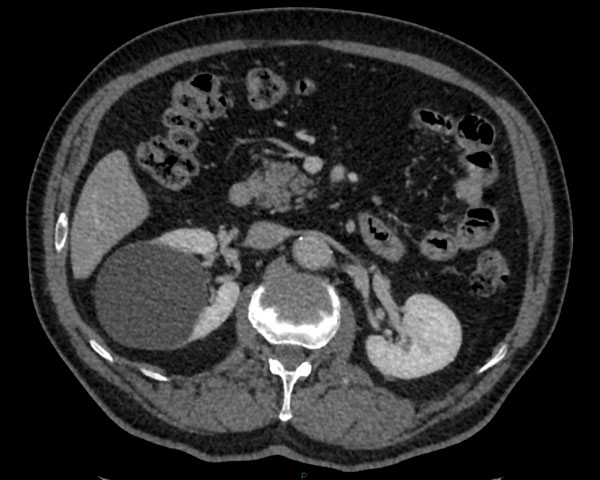

Le scanner est l’examen de référence pour apprécier les caractéristiques d’un kyste. Certains critères radiologiques comme un rehaussement de paroi, des cloisons internes multiples ou des bourgeons charnus intra kystiques incitent à surveiller ces kystes en raison du risque de malignité. En cas de forte suspicion de tumeur kystique maligne, une exérèse chirurgicale est réalisée comme pour une tumeur du rein. En revanche, la biopsie pré-opératoire n’est pas recommandée en raison du risque de dissémination des cellules malignes par perforation du kyste.

Photo : kyste atypique suspect du rein droit